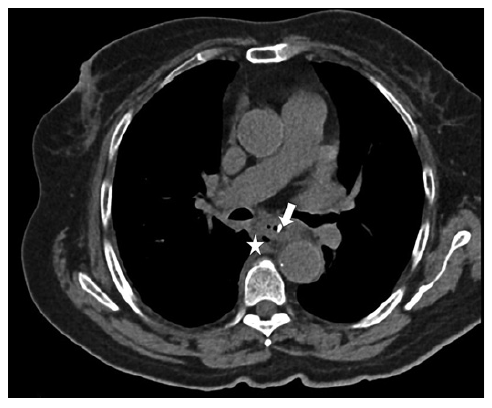

A 79-year-old diabetic woman presented at the emergency room with fever, retrosternal pain, and dysphagia 24 h after choking on pork meat. A chest CT scan without oral contrast revealed a 2 cm dense linear structure crossing the thoracic esophageal wall, with signs of pneumomediastinum and densification of the periesophageal tissues (shown in Fig. 1) - these findings were compatible with mediastinitis due to esophageal perforation by bone.

Fig. 1. Axial CT scan of admission showing the 2 cm linear structure crossing the thoracic esophageal wall (arrow) causing densification of periesophageal tissues and signs of pneumomediastinum (star).